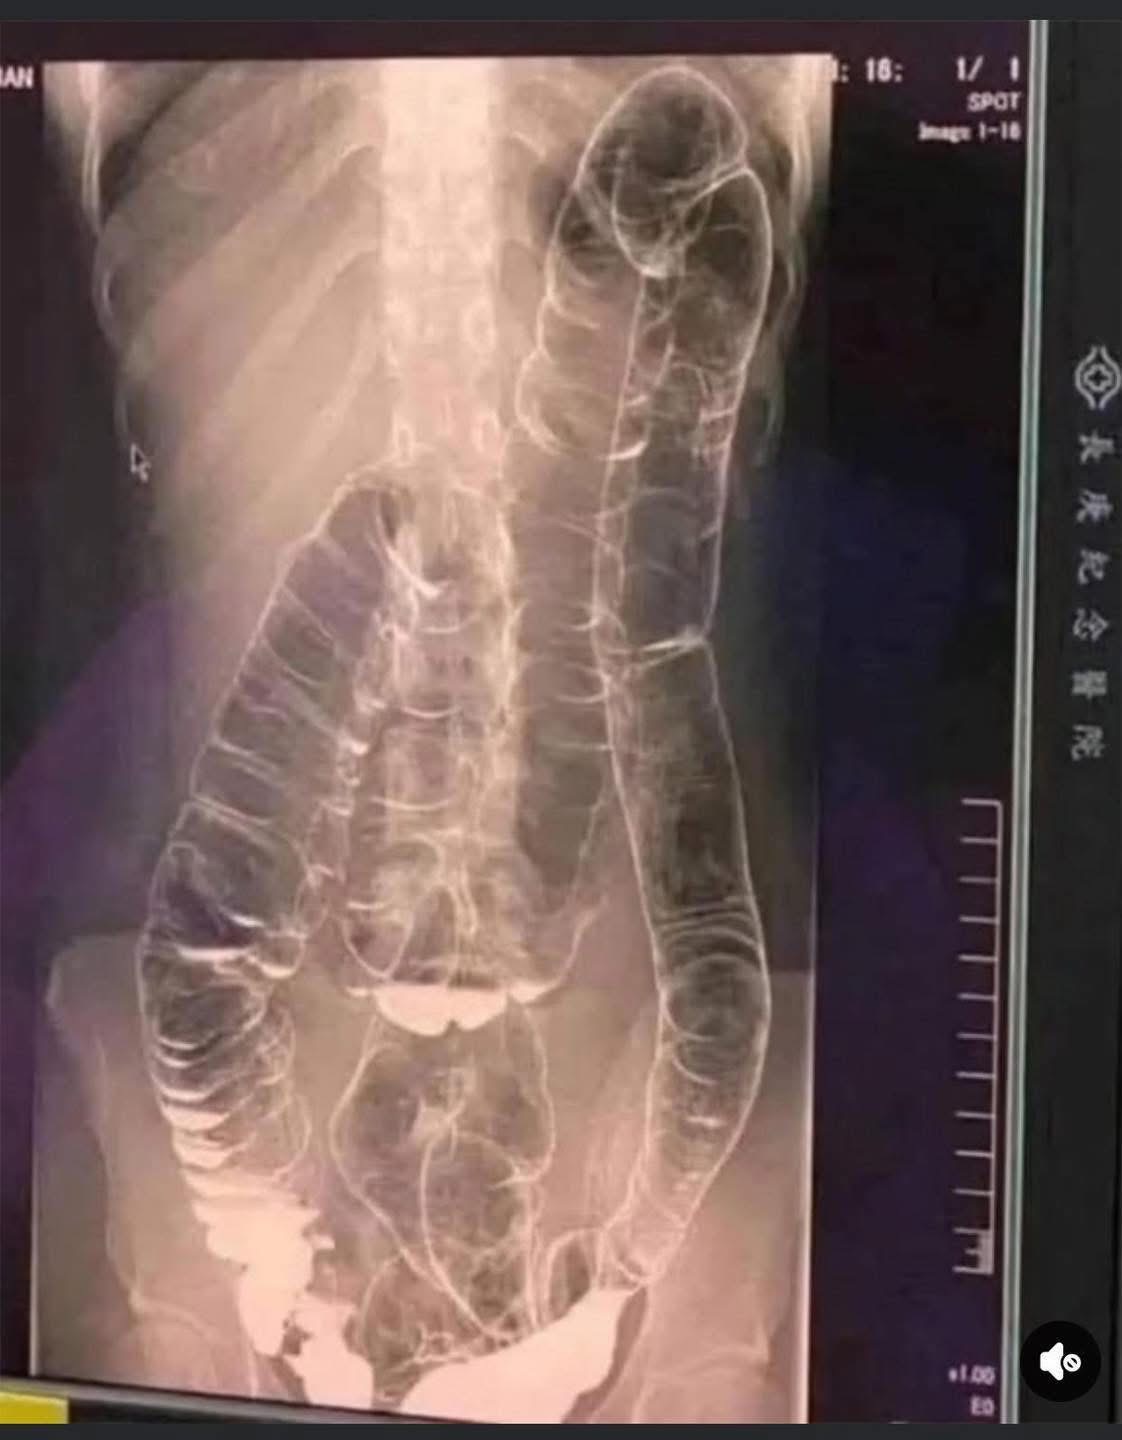

Although constipation may seem like a minor inconvenience, ignoring it for extended periods can lead to serious health complications. A striking real-life case demonstrates just how dangerous chronic constipation can be and why it should never be taken lightly. A young woman suffering from years of chronic constipation experienced a severe decline in her condition when she went more than two weeks without a bowel movement. Concerned about her worsening symptoms, she finally sought medical attention, only to receive alarming news.When waste accumulates in the colon due to an inefficient digestive system, it causes severe discomfort and bloating. Over time, the colon expands beyond its normal size, struggling to contain the excessive buildup of feces. In this case, medical imaging revealed a severely distended colon that had enlarged so much it reached up toward the chest, dangerously close to the heart. The stretching had nearly erased the colon’s natural folds and wrinkles, essential for its proper function. Left untreated, this condition could have led to life-threatening complications.

One of the most dangerous effects of chronic constipation is severe colon distension. When the colon becomes overstretched, it loses its ability to contract properly, making bowel movements increasingly difficult. This leads to a vicious cycle in which waste remains in the body for even longer periods, further aggravating the problem.